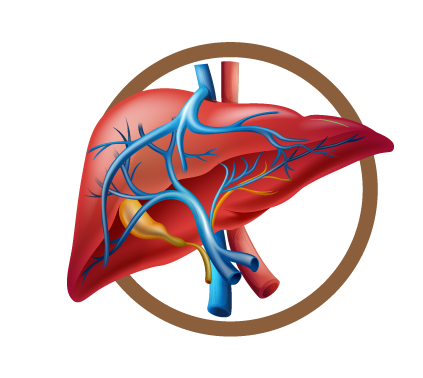

Causas del Hígado graso

El diagnostica el grado de hígado graso a través de una ecografía, también lo relaciona con los síntomas que presenta el cuerpo. Por ejemplo, si al comer sientes malestares estomacales, diarreas esporádicas, dolor abdominal, picazón al cuerpo o escamas en las manos.

Se asocian los síntomas con los resultados de las enzimas hepáticas. En el cuarto grado el hígado comienza a tener estructuras que se comienzan a dañar, y termina secándose en forma de pasa.

El hígado produce hormonas, defensas, vitamina k. Por eso, es tan importante hacer una buena prevención, porque no existe mejor medicamento que la prevención.

Te damos 5 consejos prácticos para prevenir el Hígado Graso:

1.- La alimentación es el punto clave, tu dieta debe contener los macronutrientes necesario para llenarte de energía y mantenerte saludable. Debes lograr un equilibrio entre comidas, pero lograr que prevalezca el mayor número de días la comida saludable.

2.- Un programa adecuado de ejercicio, de acuerdo a su condición física y estilo de vida será ideal.

3.- Ten buenos hábitos de higiene, eso evitara que tu cuerpo esté contaminado y que lo que ingresa a él, no perjudique al hígado.

4.- Limpia tu organismo con productos naturales, en Labmac te ofrecemos Takure, Paico, Purgamac que son depurativos sin químicos.

5.- Tomar 2 litros de agua al día.

El hígado graso si es reversible, la cirrosis no.